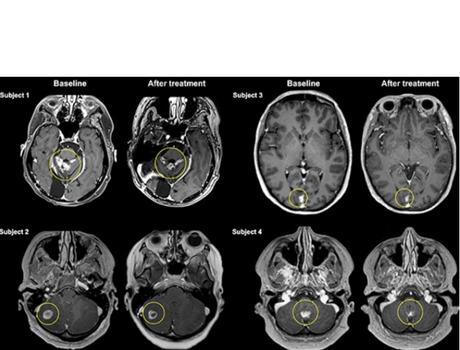

Il s’agit précisément de la publication de résultats préliminaires, chez 4 patientes de l’essai mené au total auprès de 10 participantes atteintes de cancer du sein métastatique, ou cancer du sein de stade IV, un type de cancer qui s’il prend naissance dans le sein s’est propagé au cerveau, aux os, au foie ou à d’autres organes. Les traitements actuels des métastases cérébrales du cancer du sein comprennent la neurochirurgie ouverte, la radiothérapie et la chimiothérapie. Cependant, la chirurgie et la radiothérapie sont souvent limitées par l’emplacement et le nombre de métastases cérébrales.

Ultrasons focalisés = plus d’efficacité : c’est la conclusion de cette analyse préliminaire, de l’efficacité du traitement, de l’évolution de la taille des tumeurs (soit une réduction moyenne de 21 %). Une réduction prometteuse de la taille des tumeurs mais qui doit encore être interprétée avec prudence dans l’attente de recherches supplémentaires.